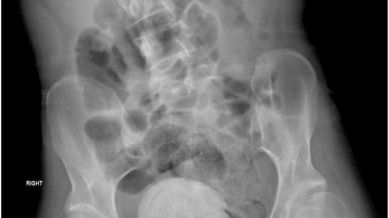

Fieber, Schüttelfrost, Erbrechen – das war nur ein Teil der Symptome, der eine 27-Jährige den Notfall aufsuchen liess. Ihr aufgeblähter Bauch liess die Ärzte schliesslich aufhorchen. Schuld war ein Fremdkörper...weiterlesen »

Oh mein Gott! Einer 27-Jährigen aus dem Libanon wurde ein Vaginalstein entfernt, der die Größe einer Orange (!) hatte. Die unglaubliche Geschichte – und was genau es damit auf sich hat. RTL.de ist jetzt...weiterlesen »

Beirut – Die Ärzte konnten kaum glauben, was sie sahen! Eine Frau aus dem Libanon schleppte sich mit Fieber, Schüttelfrost und Erbrechen in ein Krankenhaus im Libanon. Um alle Ursachen abzuklären, machten...weiterlesen »